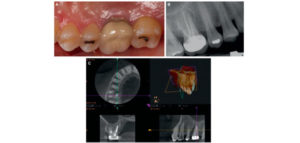

158 – Uso intraoperatorio de la CBCT para la identificación y localización de canales calcificados

Se sabe que la tomografía computarizada de haz cónico (CBCT) produce exploraciones tridimensionales de la dentición, las estructuras duras maxilofaciales y la relación de las